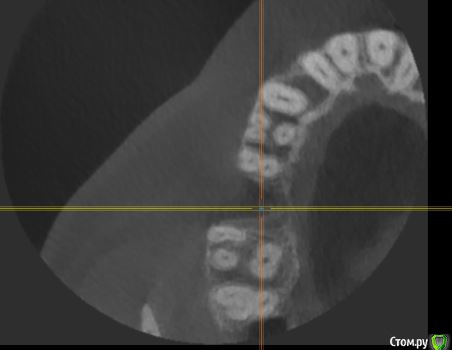

Федор С Опубликовано 1 февраля, 2018 Поделиться Опубликовано 1 февраля, 2018 Здравствуйте!Подскажите, пожалуйста, как лучше поступить в моей ситуации. Предыстория такова: из-за некачественно сделанной в свое время коронки, под верхней правой шестеркой образовалась киста. После грубого удаления зуба, образовалась большая дырка.Вопрос в следующем: ставить мост или попытаться нарастить костную ткань и поставить имплант?Сам больше склоняюсь к имплантации, но смущает, что дефект очень большой, в объеме около одно кубического см.Фото прикладываю, так же на всякий случай прикладываю ссылку на КТ (КТ делал в "Пикассо") КТ только папка DATA с диска - http://fayloobmennik.cloud/7187773Если не будет открываться, КТ весь диск целиком - http://fayloobmennik.cloud/7187772 Заранее спасибо! Ссылка на комментарий